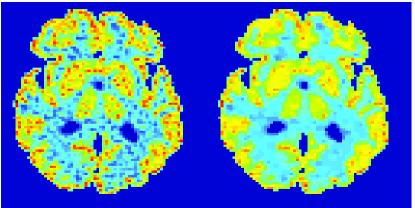

In the images shown in the figures we illustrate the calculated uptake rates of the FDG. Images for the CMRGlc can be obtained by directly scaling . In figure 1 we compare the result of using Patlak and TV-Patlak for estimating the uptake rates with respect to no noise, noise in the input function, Poisson noise in the sinogram, and finally with respect to the case in which the irreversibility assumption is violated but without noise in the sinogram or input data. In each case the histogram of the relative errors is given on the left, the Patlak image in the middle and the TV-Patlak on the right. The different scales in the histograms are due to the total number of results illustrated. When there is no noise (triples and ) the histogram illustrates results over all voxels but only one simulation, while for the noisy simulations the results are for all voxels over all realizations of the noise. The TV-Patlak images are more homogeneous in all cases and the relative errors are smaller. The figures clearly show the improvements of employing the TV-Patlak method as compared to using Patlak independently for each voxel. This is confirmed in figure 2 in which images with noise in the sinogram, positive and different noise levels in the input function are shown.